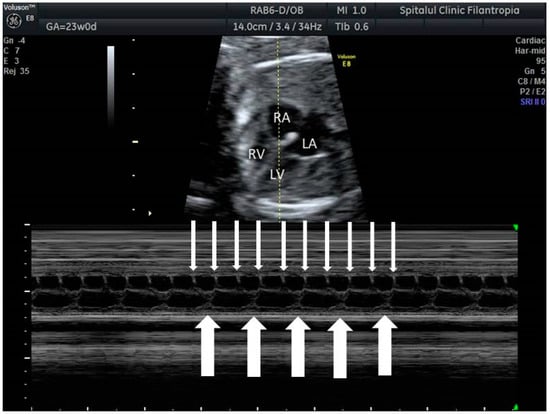

2. The Use of Ultrasound to Assess Fetal Heart Rhythm